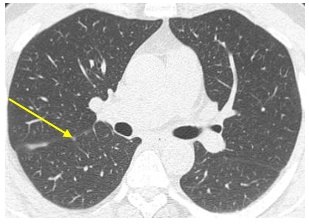

Chụp cắt lớp vi tính lồng ngực: Hình ảnh các nốt kính mờ rãnh liên thùy và màng phổi phải. Đám dải xẹp phổi thùy giữa phổi phải

Hình 8: Hình ảnh chụp cắt lớp vi tính lồng ngực sau 9 tháng điều trị